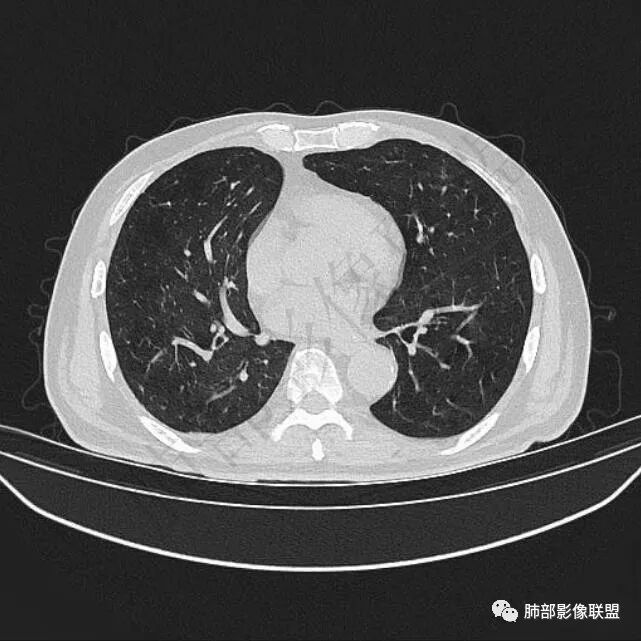

9个月后病灶明显增大,边缘较平直,部分膨隆,锁扣样外观,仍旧缺乏典型深分叶及张力,未见胸膜凹陷。

再1个多月后病灶继续增大,较明显不均匀强化,肺门一侧见低密度区。病灶边缘相对不清,可见毛刺。

三.病程脉络相当清楚,即病灶进行性增大,易想到新生物或转移瘤,但经验上分析增长速度显然太快,尤其是对于原发肺腺癌或者肺鳞癌而言,单发转移瘤也较少这样的进展速度。

四.单就影像而言,病灶肿瘤特征不够充分,恶性肿瘤病史,隐球菌等特殊感染确实不能排除。

五.尽管本例鳞癌的病例意见出乎预料,但部分低分化肿瘤迅速增长也不时出现,仍须警惕!